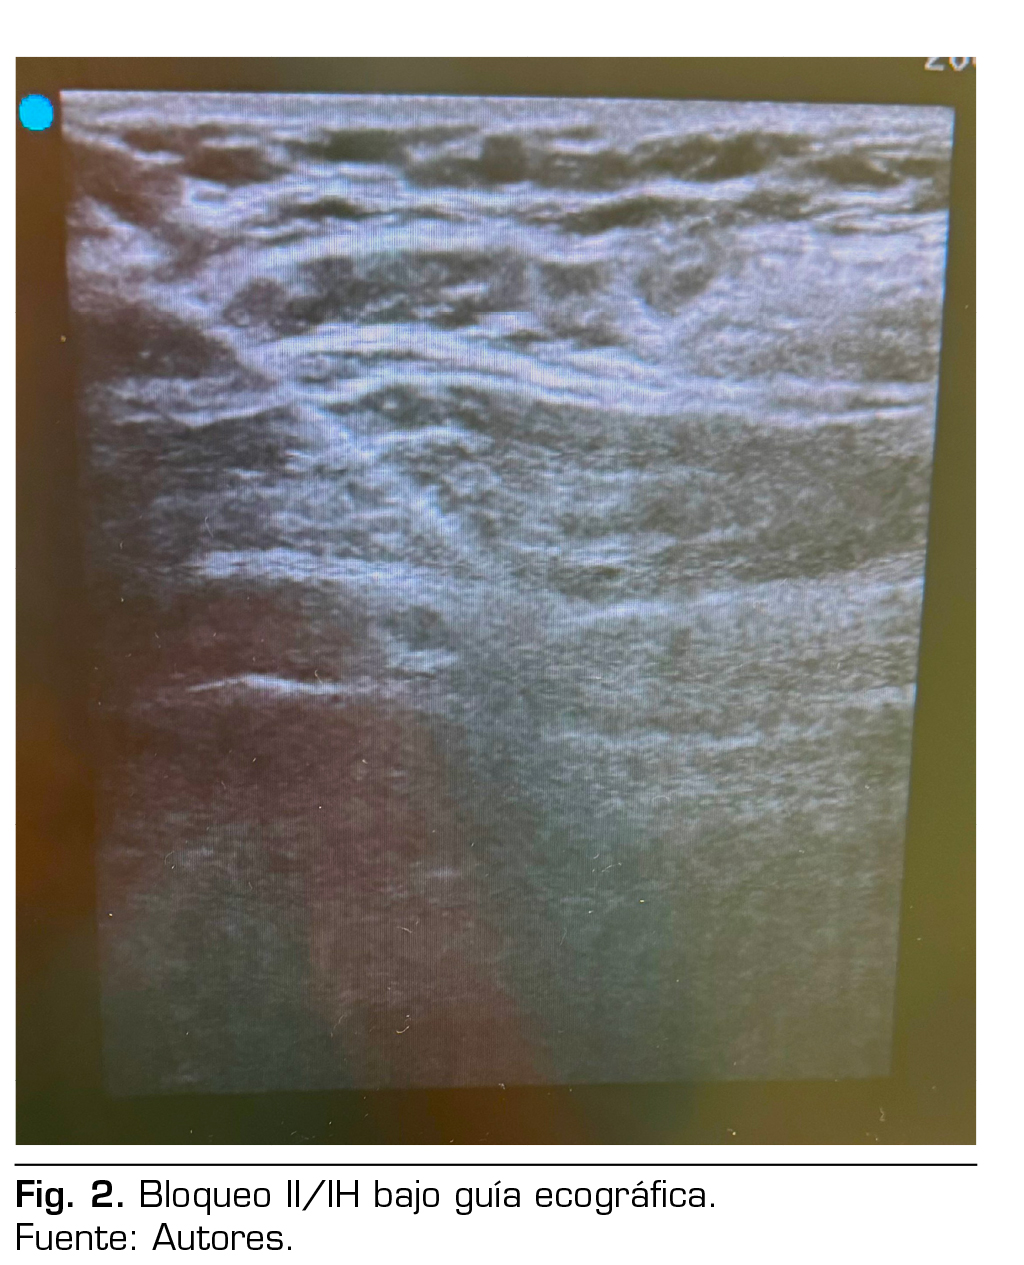

Figura 1

Presentación de caso: Presentamos el caso clínico de un paciente adulto mayor de 88 años ASA III, sometido a una hernioplastia inguinal electiva, bajo anestesia regional: bloqueo II/IH bajo guía ecográfica más sedación, manejo analgésico complementario con paracetamol y antinflamatorios, alta de cirugía médica ambulatoria a su domicilio y control postoperatorio sin complicaciones.

Case presentation: We present the clinical case of an 88-year-old adult patient ASA III, for elective inguinal hernioplasty, under regional anesthesia: Ilioinguinal-Iliohypogastric block under ultrasound guidance plus sedation, complementary analgesic management with paracetamol and anti-inflammatory drugs, discharge from outpatient surgery to his home and postoperative control without complications.